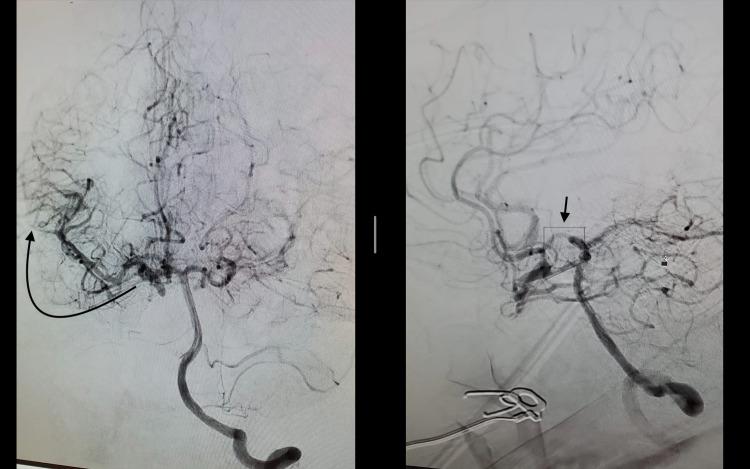

Bilateral internal carotid artery occlusion (BICAO) is a rare disease leading to serious cerebrovascular disease and complications including recurrent ischemic stroke or death. There are very few cases reported on BICAO, especially among young adults. The clinical presentation can range from asymptomatic to fatal ischemic stroke depending upon the presence of adequate collateral blood flow. Here we report a case of BICAO in a 31-year-old female who presented with intermittent left-sided hemiparesis for one day and was subsequently found to have complete occlusion of the bilateral intracranial internal carotid arteries on CT angiography (CTA). Magnetic resonance imaging (MRI) brain showed sub-acute right middle cerebral artery (MCA), acute left middle cerebral artery, and anterior cerebral artery infarcts (ACA). Being outside the window for thrombolysis, she was successfully treated with balloon angioplasty of the left internal carotid artery (ICA) and started on dual antiplatelet therapy. The case illustrates the importance of evaluating for cerebrovascular disease when someone presents with stroke-like symptoms even in the young adult population, as prompt treatment can be lifesaving.

双侧颈内动脉闭塞(BICAO)是一种罕见疾病,可导致严重的脑血管疾病及包括复发性缺血性卒中或死亡在内的并发症。关于BICAO的病例报道极少,尤其是在年轻成年人中。临床表现因是否存在充足的侧支血流而异,从无症状到致命性缺血性卒中不等。在此,我们报告一例31岁女性的BICAO病例,该患者出现间歇性左侧偏瘫1天,随后在CT血管造影(CTA)检查中发现双侧颅内颈内动脉完全闭塞。脑部磁共振成像(MRI)显示右大脑中动脉(MCA)亚急性梗死、左大脑中动脉急性梗死以及大脑前动脉(ACA)梗死。由于已过溶栓时间窗,她接受了左侧颈内动脉(ICA)球囊血管成形术治疗并成功治愈,随后开始双联抗血小板治疗。该病例表明,即使在年轻成年人群中,当有人出现类似卒中症状时,评估脑血管疾病非常重要,因为及时治疗可挽救生命。